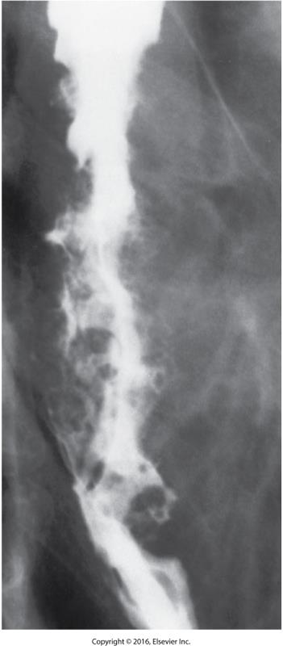

Esophageal Varices

Dilated veins in the distal esophagus.

Caused by portal hypertension.

May bleed.

Radiological Appearance

Wavy border, thickening folds

Appear as round or oval filling defects (beads